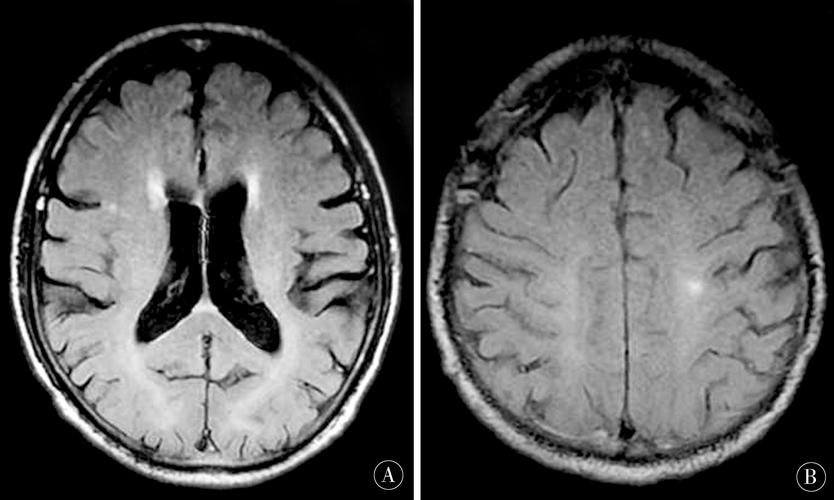

腔隙性脑梗mri表现

(图片来源网络,侵删)

• DWI/ADC:信号通常恢复正常,呈等信号。

• T2/FLAIR:病灶持续呈高信号,代表胶质增生和囊腔形成。

• T1加权像:病灶最终形成边界清晰的低信号(脑脊液样信号),即“腔隙”(Lacune),这是“腔隙性脑梗死”名称的由来。

• 磁敏感加权成像:如果梗死灶内有微量出血,SWI上可能会看到微小的低信号影(含铁血黄素沉积)。